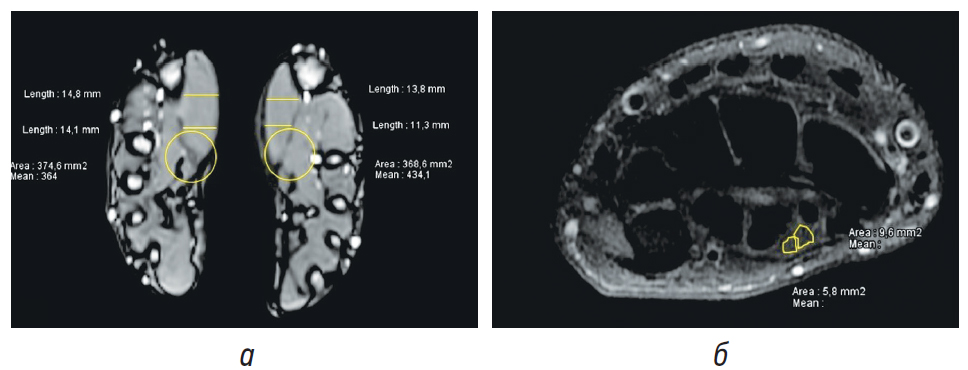

№ 3. Пациент Б. 26 лет. Компрессионно-ишемическая невропатия левого срединного нерва на уровне запястного канала с развитием КРБС II типа. С его слов и согласно медицинской документации, при сдаче нормативов по физической подготовке получил травму левой кисти и левого лучезапястного сустава (краевой перелом левой III пястной кости). Через 3 мес выполнялась операция — удаление костно-хрящевого экзостоза левой кисти. Позднее тенолиз разгибателей левой кисти. Через 2 года после операций на фоне физических нагрузок появилась острая боль высокой интенсивности до 8–9 баллов по ВАШ с последующим сохранением болевого синдрома до 3–4 баллов, не купирующегося приемом нестероидных противовоспалительных препаратов, периодически возникающее чувство онемения 1-го и 2-го пальцев левой кисти. Со слов пациента, принимал трамадол до 1500 мг/сут, прегабалин до 1200 мг/сут, затем габапентин до 3600 мг/сут, выполнялась локальная инъекционная терапия дипроспаном в область левого карпального канала без значимого положительного эффекта. При выполнении ЭНМГ — показатели легкого очагового демиелинизирующего поражения сенсорных волокон левого срединного нерва на уровне лучезапястного сустава. Длительность болевого синдрома 9 мес (рис. 4).

Рис. 4. Пациент Б; а — магнитно-резонансная томография (МРТ) кистей; б — МРТ левой кисти: желтым цветом выделены две порции срединного нерва

При выполнении МРТ кистей данных за патологию периферических нервов выявлено не было. Имелась незначительная гипотрофия мышц тенера левой кисти. При повторном анализе МРТ также было выявлено двуствольное строение срединного нерва (рис. 4).

При выполнении пациенту УЗИ левого срединного нерва: на всем протяжении был нормальной эхоструктуры, за исключением уровня линии лучезапястного сустава, где отмечался участок нерва с умеренно выраженной гипоэхогенной эхоструктурой с неравномерным диаметром нервного ствола, увеличением S сечения нерва до 21 мм2 (N — до 11 мм2). В дистальной части карпального канала срединный нерв раздваивается на 2 ствола: медиальную ветвь (S сечения нерва 14 мм2) и латеральную ветвь (S сечения нерва 10 мм2).

У пациента Б. была отмечена диссоциация между данными ЭНМГ (поражение сенсорных волокон левого срединного нерва), данными МРТ (гипотрофия мышц тенера левой кисти), а также результатами УЗИ (двуствольное строение левого срединного нерва), которая привела к несвоевременной диагностике заболевания и хронизации болевого синдрома.